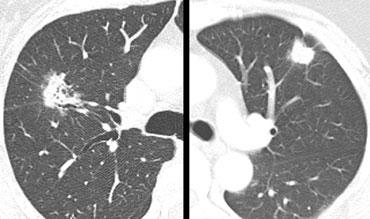

Bên trái là hai nốt phổi đơn độc.

Dựa trên hình thái học, tổn thương nào có đặc điểm ác tính nhất?

Tổn thương ở ngoài cùng bên trái có bờ tua gai và có các vùng sáng bên trong.

Tổn thương kế bên có bờ múi và một số tua gai tỏa ra màng phổi.

Tuy nhiên, tổn thương này đồng nhất về tỷ trọng.

Dựa trên các phát hiện này, chúng ta cần lo ngại nhất rằng tổn thương ở ngoài cùng bên trái là ác tính.

Tổn thương đó được xác nhận là ung thư biểu mô tuyến, trong khi tổn thương kia là nhiễm nấm.

Các vùng sáng và dấu hiệu phế quản hơi rõ ràng không nên khiến bạn nhầm lẫn rằng đó có thể là nhiễm trùng.